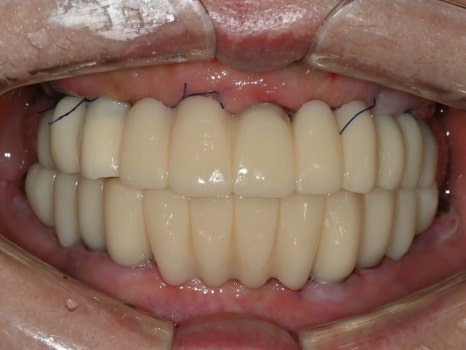

수술 후

디지털 방식으로 제작된 임시치아

8개의 전체임플란트를

하루에 바로 수술할 수 있었고,

병원 내의 디지털기공소에서

바로 임시치아를 제작하였습니다.

수술 전

수술 1일 후

하루만에 위턱 전체 치아가 생겨서

식사가 바로 가능하시게 되자

환자분은 너무 놀라워하시고 좋아하셨습니다.